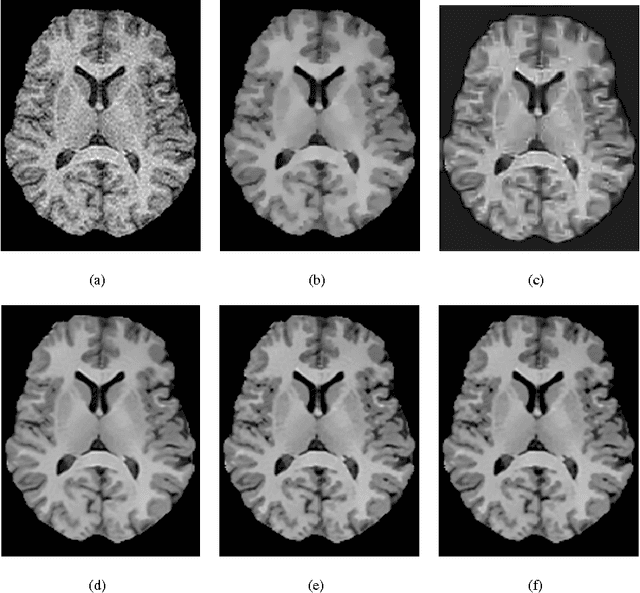

Abstract:The acquisition of MRI images offers a trade-off in terms of acquisition time, spatial/temporal resolution and signal-to-noise ratio (SNR). Thus, for instance, increasing the time efficiency of MRI often comes at the expense of reduced SNR. This, in turn, necessitates the use of post-processing tools for noise rejection, which makes image de-noising an indispensable component of computer assistance diagnosis. In the field of MRI, a multitude of image de-noising methods have been proposed hitherto. In this paper, the application of a particular class of de-noising algorithms - known as non-local mean (NLM) filters - is investigated. Such filters have been recently applied for MRI data enhancement and they have been shown to provide more accurate results as compared to many alternative de-noising algorithms. Unfortunately, virtually all existing methods for NLM filtering have been derived under the assumption of additive white Gaussian (AWG) noise contamination. Since this assumption is known to fail at low values of SNR, an alternative formulation of NLM filtering is required, which would take into consideration the correct Rician statistics of MRI noise. Accordingly, the contribution of the present paper is two-fold. First, it points out some principal disadvantages of the earlier methods of NLM filtering of MRI images and suggests means to rectify them. Second, the paper introduces a new similarity measure for NLM filtering of MRI Images, which is derived under bona fide statistical assumptions and results in more accurate reconstruction of MR scans as compared to alternative NLM approaches. Finally, the utility and viability of the proposed method is demonstrated through a series of numerical experiments using both in silico and in vivo MRI data.